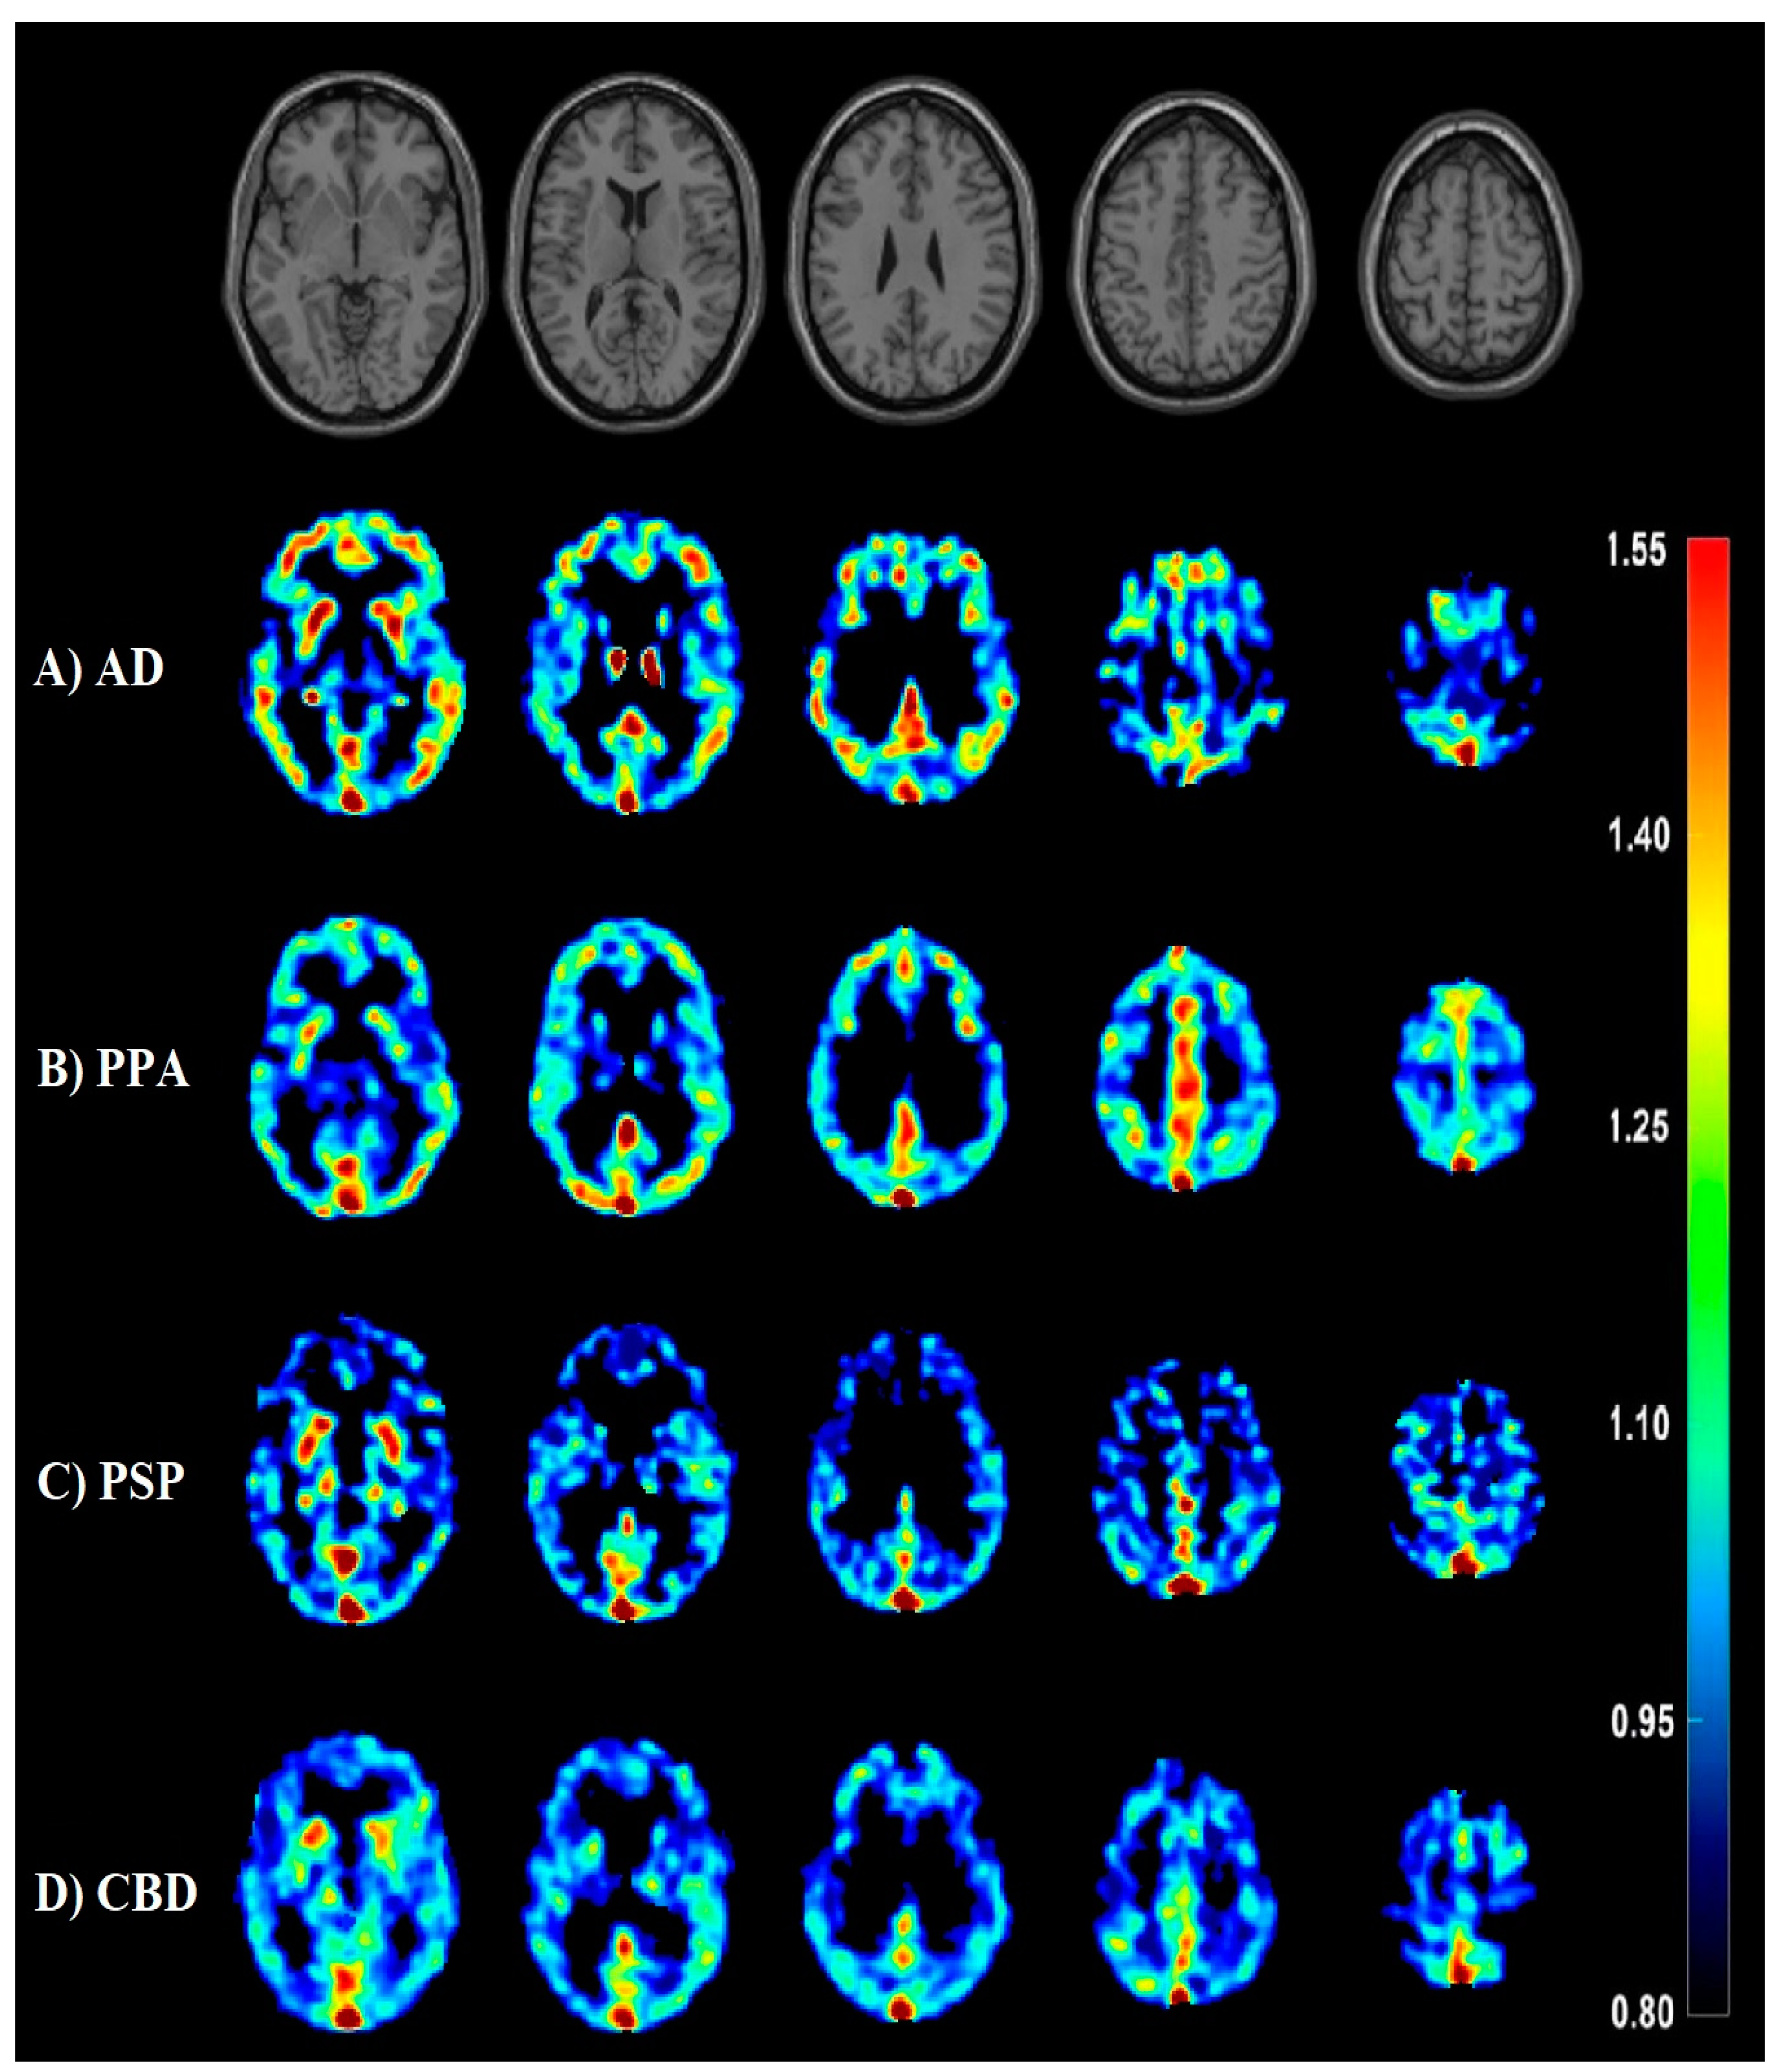

- Minoshima, S.; Cross, D.; Thientunyakit, T.; Foster, N.L.; Drzezga, A. 18F-FDG PET Imaging in Neurodegenerative Dementing Disorders: Insights into Subtype Classification, Emerging Disease Categories, and Mixed Dementia with Copathologies. J. Nucl. Med. 2022, 63, 2S–12S. [Google Scholar] [CrossRef]

- Nestor, P.J.; Altomare, D.; Festari, C.; Drzezga, A.; Rivolta, J.; Walker, Z.; Bouwman, F.; Orini, S.; Law, I.; Agosta, F.; et al. Clinical utility of FDG-PET for the differential diagnosis among the main forms of dementia. Eur. J. Nucl. Med. Mol. Imaging 2018, 45, 1509–1525. [Google Scholar] [CrossRef]